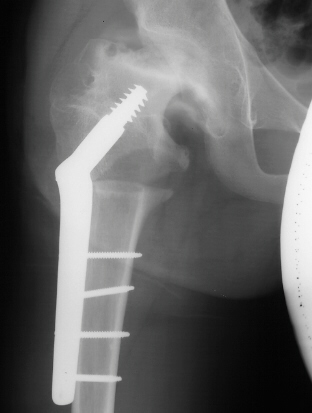

- Age 6: Valgus osteotomy for subluxation and 2cm leg length inequality.

- Age 15: Valgus osteotomy for hip incongruity.